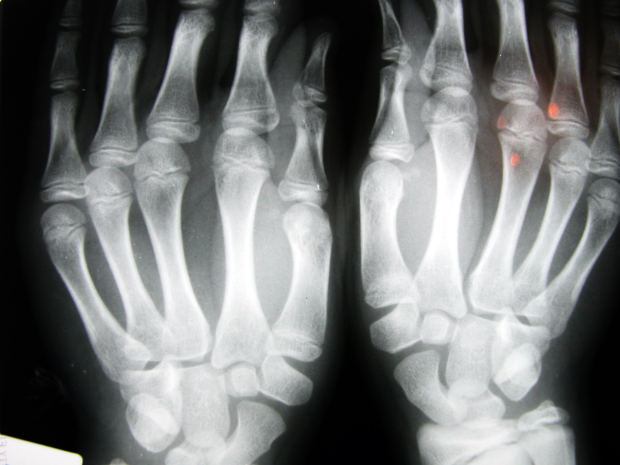

Stosowanie marihuany w celach leczniczych w ostatnim czasie budzi wyjątkowe zainteresowanie naszych polityków. Naukowcy od dawna zajmują się jej dobroczynnymi właściwościami. Tym razem badacze z Tel Avivu dowodzą, że marihuana przyspiesza proces leczenia złamań kości.

Wynika tak z ich najnowszych badań. „The Times of Israel”, poinformował o odkryciu naukowców z Tel Avivu. Dowodzą oni, że szczury ze złamaniami kończyn szybciej dochodziły do zdrowia, jeśli podawano im kannabidiol (CBD), organiczny związek chemiczny występujący w konopiach.

Zauważono, iż kości zwierząt wyleczonych przy zastosowaniu takiej terapii były znacznie mocniejsze i odporniejsze na urazy. Zdaniem badaczy oznacza to, że przyjmowanie marihuany zmniejsza ryzyko ponownego złamania.

– Odkryliśmy, że CBD może wspomagać proces leczenia kości. Wiele innych badań wykazało, że właściwości marihuany mogą być wykorzystywane w bezpieczny sposób. To wszystko prowadzi nas do wniosku, że badania nad nią powinny być kontynuowane – przekonuje dr Yankel Gabet.